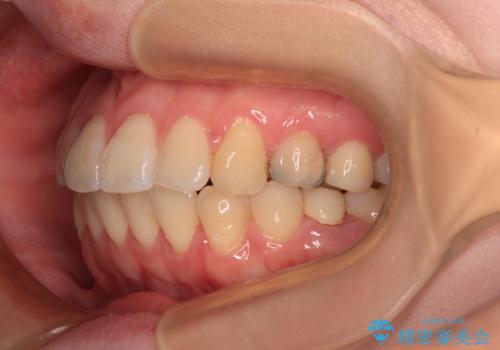

開咬と前方に飛び出した前歯 インビザラインによる矯正治療

- 上下前歯の非接触と叢生を気にして来院された患者様です。

開咬の改善はインビザラインの最も得意とするところであるため、インビザラインを用いて矯正治療を行うこととしました。

舌の突出癖改善のトレーニングをしっかりと行っていただき、上下前歯が接触する咬み合わせを達成することができました。